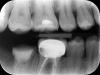

ethene Опубликовано 1 марта, 2010 Поделиться Опубликовано 1 марта, 2010 На снимке - 6-й под коронкой и 7-й замучаный зуб (две перфорации, скол под десну).На 6-м потемнение на снимке (киста?)Оба зуба предлагают под удаление, но, сами понимаете, не хочется.Есть ли шансы лечить хотя бы 6-й? Ссылка на комментарий

Sir Edward'S Опубликовано 1 марта, 2010 Поделиться Опубликовано 1 марта, 2010 На снимке - 6-й под коронкой и 7-й замучаный зуб (две перфорации, скол под десну).На 6-м потемнение на снимке (киста?)Оба зуба предлагают под удаление, но, сами понимаете, не хочется.Есть ли шансы лечить хотя бы 6-й? лучше оба зуба удалить так как разрушены ниже уровня десны Ссылка на комментарий